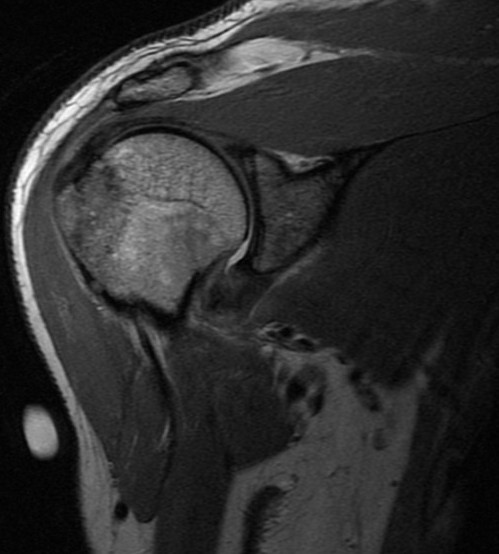

Injury. Possible dislocation

Subluxation or dislocation can result in a GT fx (essentially a hill sachs that progresses anteriorly). Rather than a bankart lesion, many times a capsular sprain will result without a labral detachment. The thickened edematous capsule will look like adhesive capsulitis but in this case has the traumatic history often not there with adhesive capsulitis.

Greater tuberosity fracture and capsular sprain